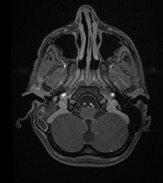

Diagnostic testing. Findings from the laboratory studies revealed an elevated white blood cell count of 33.09 c/mL, an elevated erythrocyte sedimentation rate of 122 mm/hr, and an elevated procalcitonin level of 9.61 ng/mL. Thus, the patient was started on cefepime and levetiracetam. Imaging studies demonstrated mastoiditis, a large right temporal collection of fluid concerning for early cerebritis, and ventriculitis with abscess formation and local mass effect (Figures 1-4).

Figure 4. Postcontrast axial magnetic resonance imaging demonstrated (a, top) mastoiditis and (b, bottom) a right temporal lobe abscess decompressing into the ventricular system, with presence of ventricular abscesses.